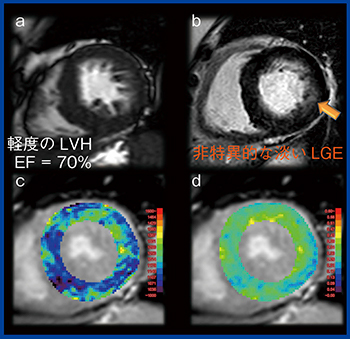

症例1は,60歳代,女性で心電図異常と心肥大を指摘されてMRIを施行した。シネMRとLGEイメージングでは,EF(=70%)は保たれ,軽度の左室肥大(LVH)が認められるが,梗塞壁に淡い斑状のLGEがある非特異的な所見で,何らかの心筋症としか判断できない。T1マッピングではECVは正常値だが,Native T1で有意な低下(950〜1100ms,施設基準値:1250ms)を認めた。Native T1は脂質の沈着で短縮するため心ファブリー病が疑われた(図1)。遺伝子検査でファブリー病と診断され,酵素補充療法が実施された。

図1 症例1:60歳代,女性,ファブリー病

a:シネMR b:LGE c:Native T1 d:ECV